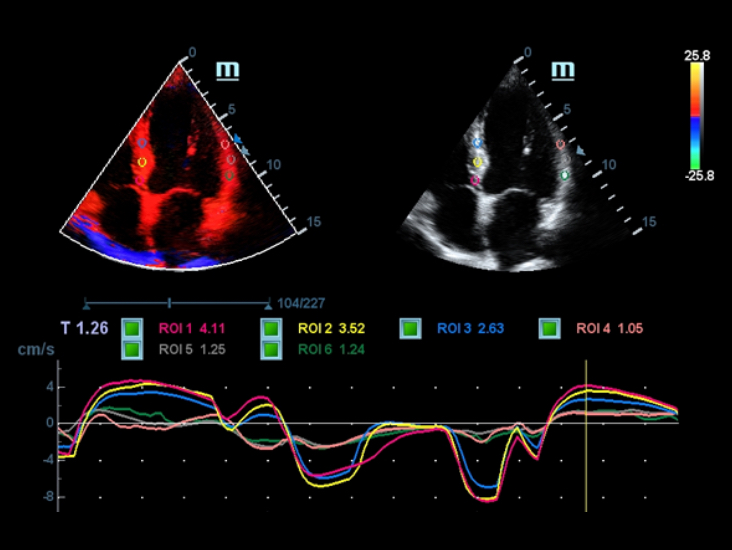

Smart Track

Con un semplice tocco, Smart Track consente di ottenere una visualizzazione ottimizzata rapida e intelligente dell'imaging vascolare. ? in grado di ottimizzare lo spettro del colore, del power e del PW mediante il funzione di tracking automatico e ridurre i passaggi che richiedono molto tempo, semplificando cosĂŹ il flusso di lavoro per gli esami vascolari.